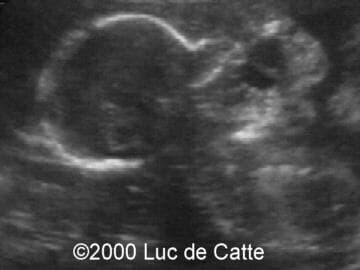

The following structural defects were observed:

• anterior mass,

• emanating from the fetal mouth,

• partly cystic, partly solid

• no calcifications

This 32-year-old primigravida patient was referred at the ultrasound department at 19.5 weeks of gestation for a second opinion concerning a fetal facial mass. Scanning revealed a large, mixed tumor emanating from the pharynx and mouth. The fetal position did not allow for other congenital anomalies to be observed. The diagnosis of epignathus was made.

Epignathus (from the greek epi = above and gnaqos = jaw) represents a rare congenital teratoma arising from the palate or pharynx in the region of the sphenoid (Rathke's pouch)1,2. It may involve the sphenoid bone, pharynx, tongue and jaw. Although it may vary greatly in size and texture, epignathus generally extends through the mouth and creates an anterior facial mass. There is no known genetic or recurrence risk or predisposing factors.

Most are diagnosed by ultrasound scanning in the late second and third trimesters, although early diagnosis at 151 and 17 weeks of gestation3 have been reported. A large mixed solid-cystic and sometimes calcified tumor projecting from the oral cavity suggests the diagnosis. Because the tumor can interfere with swallowing, polyhydramnios can be present3. Occasionally, a large and vascular epignathus may lead to high-output cardiac failure and subsequently to a non-immune hydrops fetalis.